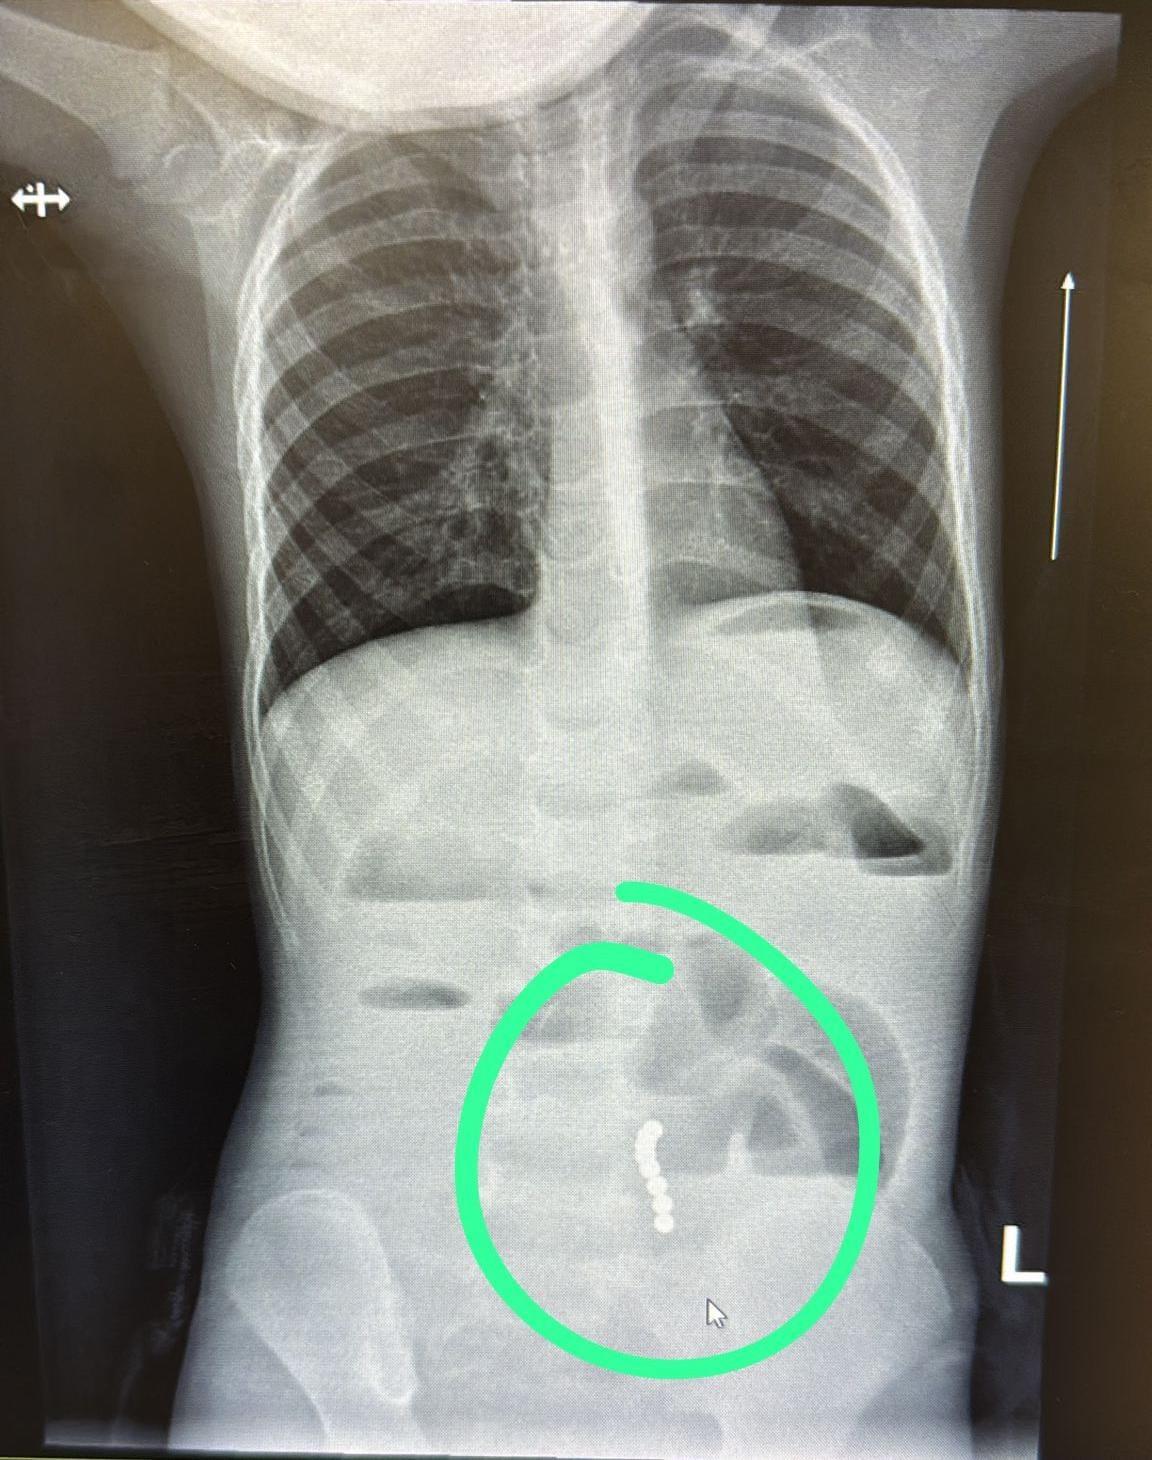

פעוט בן 4 בלע שמונה מגנטים – נותח בדחיפות ושוחרר לאחר שבוע אשפוז‎

הרופאים זיהו הקאות חריגות שהובילו לאבחון מהיר של חסימת מעי מסוכנת; בבית החולים מזהירים: מגנטים עלולים לגרום לנמק ואף לנקב במעי הפוסט פעוט בן 4 בלע שמונה מגנטים – נותח בדחיפות ושוחרר לאחר שבוע אשפוז הופיע לראשונה ב-JDN.